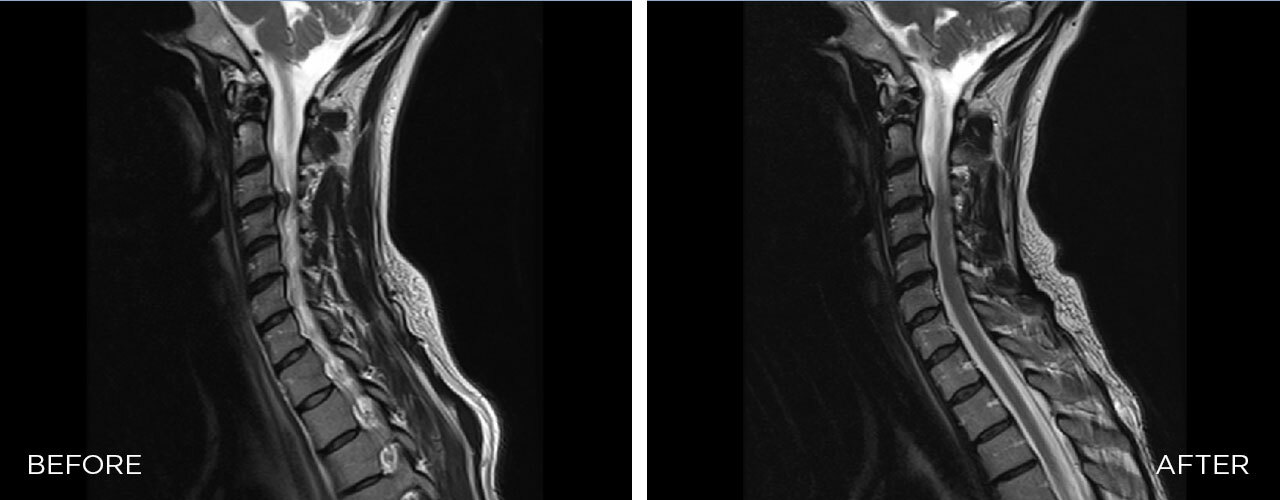

Mechanism of Action

SPINAL DECOMPRESSION is a mechanical therapy that uses automated decompressive forces to mobilise joints, relieve the pressure over neuro-spinal structures, and relax and elongate soft tissues.

Neck Pain

We produce the very first automated decompression for neck pain that perfectly substitutes manual therapy without compromising clinical outcomes.